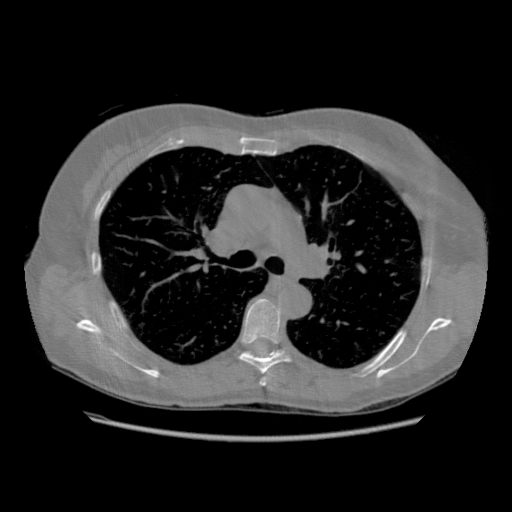

IV-C Few-View CT Reconstruction

In this section, the reconstruction performance of our proposed framework under few-view conditions will be tested. For the parallel and fan beam geometry, the number of views increases from to , uniformly distributing from to and to respectively. Such settings provide a complete benchmark of reconstruction performance, ranging from extremely sparse to relatively complete, full-view CT reconstruction. The experiment results are shown in Fig.5. Additionally, the ground truth, few-view ( views), and full-view ( views) CT reconstruction results of different methods are shown in the first and third rows of Fig.7 (parallel-beam, LIDC-IDRI dataset), and Fig.8 (fan-beam, LIDC-IDRI dataset).

To test the proposed framework’s performance on limited-angle reconstruction, we redo the experiment in the above section with the angular range changing from to for parallel-beam geometry and to for fan-beam geometry, one projection per degree. The experiment results are shown in Fig.6. Also, the ground truth and the limited-angle CT reconstruction results of different methods are shown in the row of Fig.7 (parallel-beam, LIDC-IDRI dataset), and Fig.8 (fan-beam, LIDC-IDRI dataset).

(a) Ground Truth

43.87dB/0.96

(b) ASD-POCS

47.96dB/0.97

(c) RBP-DIP

34.46dB/0.84

(d) DIP

26.63dB/0.93

(e) MED50

29.03dB/0.95

(f) RED-CNN

SNR/SSIM

16.31dB/0.55

20.83dB/0.83

13.37dB/0.61

16.65dB/0.79

13.40dB/0.73

16.85dB/0.65

22.47dB/0.78

14.25dB/0.63

22.99dB/0.62

19.51dB/0.56

30.15dB/0.85

39.35dB/0.94

27.10dB/0.78

23.88dB/0.65

20.59dB/0.60